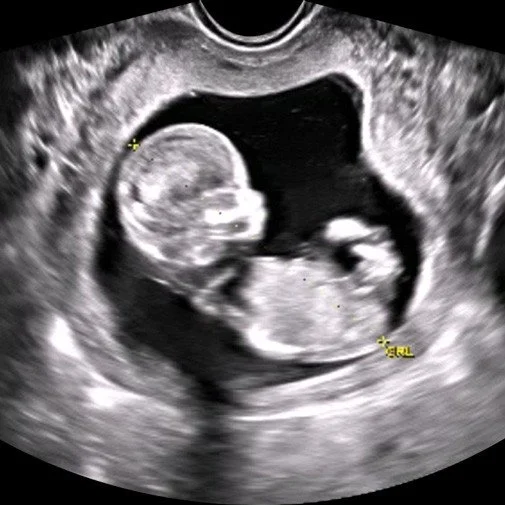

Why Do I Need an Ultrasound if I Want an Abortion?

Knowing what is actually happening during the very early stages of pregnancy is anyone’s best guess. In such a deep unknown, how do we know if the pregnancy is progressing? How do we know it is in the correct place before damage is done? And for an uncertain woman, how can she think that it is safe to undergo a chemical or surgical procedure? It is true that many women are emotionally affected by the opportunity to see a beating heart in an ultrasound, but the importance of it is imperative to ensure that her health remains the priority, regardless of her decision.